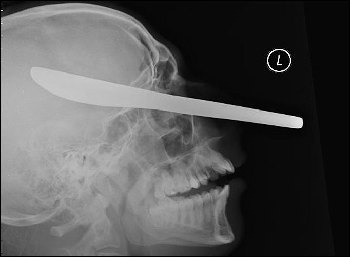

一把用來(lái)抹黃油的刀就這樣插在了受害人邁克爾的頭部。

當(dāng)醫(yī)生向邁克爾展示這張恐怖的頭部X光片時(shí),他不敢相信自己的眼睛——一把用來(lái)抹黃油的刀從他的左側(cè)臉頰穿過(guò),直達(dá)他右側(cè)的頭蓋骨,距離他的大腦只有1英寸(約2.5厘米)。

在庭上,法官尤伊斯特說(shuō):“我看過(guò)那張X光片,我只能用惡心和震驚來(lái)形容看到照片的感覺。我不能理解一個(gè)人怎么可以如此惡毒,做出這樣的事情。你(馬克)對(duì)社會(huì)沒有任何貢獻(xiàn),你必須一輩子都處于警方監(jiān)管之下?!?/p>